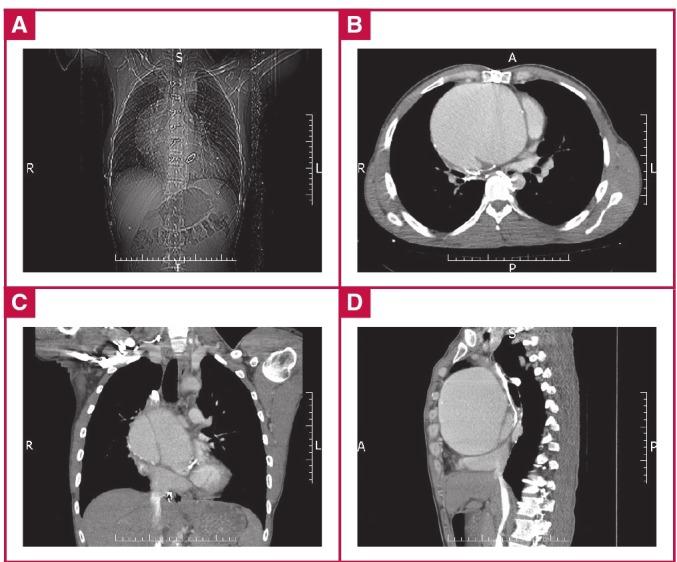

Giant aortic aneurysm is defined as an aneurysm of the aorta of greater than 10 cm in diameter. This rare condition is associated with a high risk of morbidity and mortality and it may lead to fatal complications such as rupture and/or dissection if not managed with proper surgical planning and expertise. Other than atherosclerosis, the main causes of giant ascending aortic aneurysms include Marfan and Ehlers-Danhlos syndromes. Herein we report on a young male patient who had had an aortic valve replacement five years earlier due to a bicuspid aortic valve leading to aortic failure, accompanied by aortic coarctation. He had an aneurysmal expansion rate of 1.81 cm/year to reach a final aneurysmal diameter of 13.25 cm, which, to our knowledge, represents the largest size ever reported in the literature for such lesions, and in which the redo and aneurysmal wall were adjacent to the sternal margins.

巨大主动脉瘤被定义为直径大于10厘米的主动脉瘤。这种罕见病症与高发病率和死亡率风险相关,如果没有适当的手术规划和专业技术进行处理,可能会导致诸如破裂和/或夹层等致命并发症。除动脉粥样硬化外,巨大升主动脉瘤的主要病因包括马凡综合征和埃勒斯-当洛综合征。在此,我们报告一名年轻男性患者,他五年前因二叶式主动脉瓣导致主动脉功能衰竭并伴有主动脉缩窄而接受了主动脉瓣置换术。他的动脉瘤扩张速率为每年1.81厘米,最终动脉瘤直径达到13.25厘米,据我们所知,这是此类病变在文献中报道的最大尺寸,并且再次手术区域和动脉瘤壁紧邻胸骨边缘。